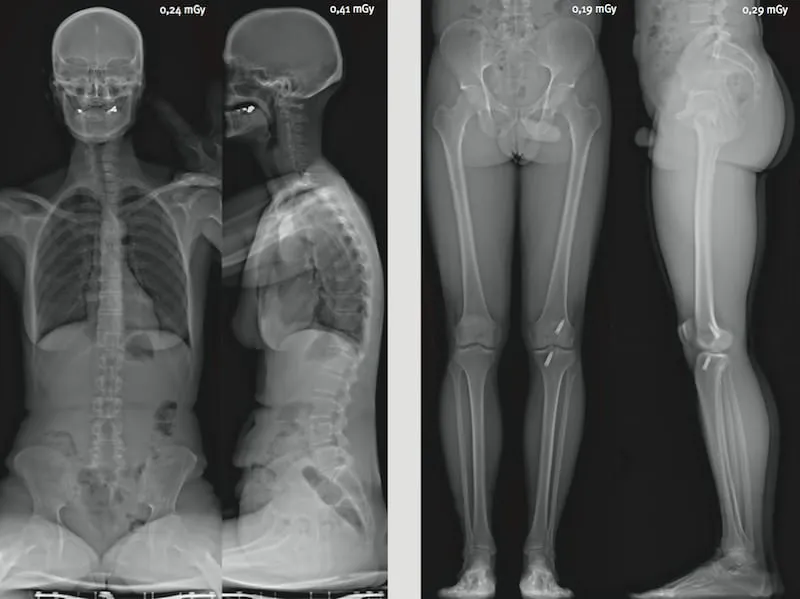

- Scoliose : suivi des courbures rachidiennes chez l’enfant et l’adolescent avec une irradiation minimale

- Bilan postural global : analyse de l’ensemble de la statique corporelle en position debout (charge physiologique)

- Bilan pré et post-opératoire : planification chirurgicale orthopédique et contrôle des résultats

- Inégalités de longueur des membres inférieurs : mesure précise et reproductible

- Pathologies rachidiennes de l’adulte : cyphose, lordose, dégénérescence discale